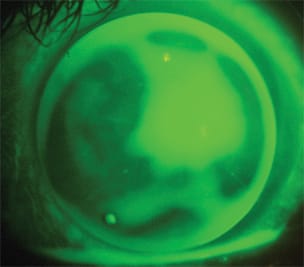

Upon dispensing, the 8.25mm diagnostic lens exhibited excessive movement and was uncomfortable. Considering that peripheral alignment, centration and comfort is desirable, the initial outcome indicated that the diagnostic lens was too flat, so we selected the next steeper lens from the fitting set. The steeper 8.20mm diagnostic lens aligned well in the periphery, centered and was comfortable to the patient (Figure 5). Because we have now determined the correct "outside" parameters, we can now evaluate the "inside" parameters.

Figure 5. 8.20mm BE Retainer diagnostic lens exhibiting good peripheral alignment and apical clearance on an oblate post-RK cornea.

The fluorescein pattern exhibited a fair amount of apical clearance over the flattened central cornea, although it was not excessive because bubbles weren't present. An over-refraction on the plano diagnostic lens revealed –1.25D, which provided the patient with 20/25 vision.